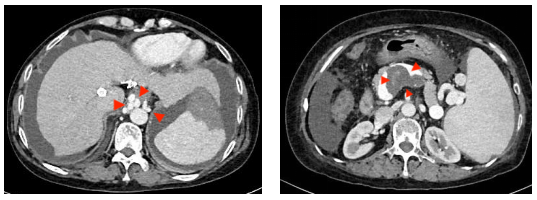

但在一周前, XX女士再次感到腹胀难忍、黑便重现,随即来到市四医院消化内科就诊。医务人员检查发现她存在大量腹水、食管胃底静脉曲张和门静脉血栓——虽然彩超显示原TIPS支架内血流通畅,但结合其病史,医务人员判断:原分流道分流量不足,导致门静脉高压问题没有真正得到解决。

手术中,在兄弟科室的全力配合下,介入团队精准测量发现何女士门静脉压力梯度高达26mmHg,证实原通道分流量严重不足。随后,医务人员经肝右静脉成功穿刺门静脉右支,在栓塞严重曲张的静脉后,建立了一条全新的8mm分流道。

术后,门静脉压力梯度骤降至7mmHg。为了避免过度分流加重心脏负担,介入团队又巧妙地利用球囊封堵原分流道后反复测量评估门静脉压力后使用弹簧圈封堵原分流道,最终将门静脉压力梯度控制在14mmHg的理想水平。